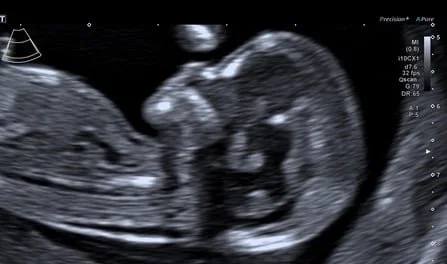

Fetale Echokardiografie, Spezialuntersuchung des kindlichen Herzens

Feindiagnostik 19+0-21+6 SSW., erweitertes Organscreening des Kindes, Beurteilung der Plazenta, Fruchtwasser, Gebärmutterhals, Durchblutung

High-End-Ultraschall

Ich arbeite mit einem „High-End-Ultraschallgerät“ der neuesten Generation, welches speziell für Pränataldiagnostik und Frauenheilkunde entwickelt wurde.